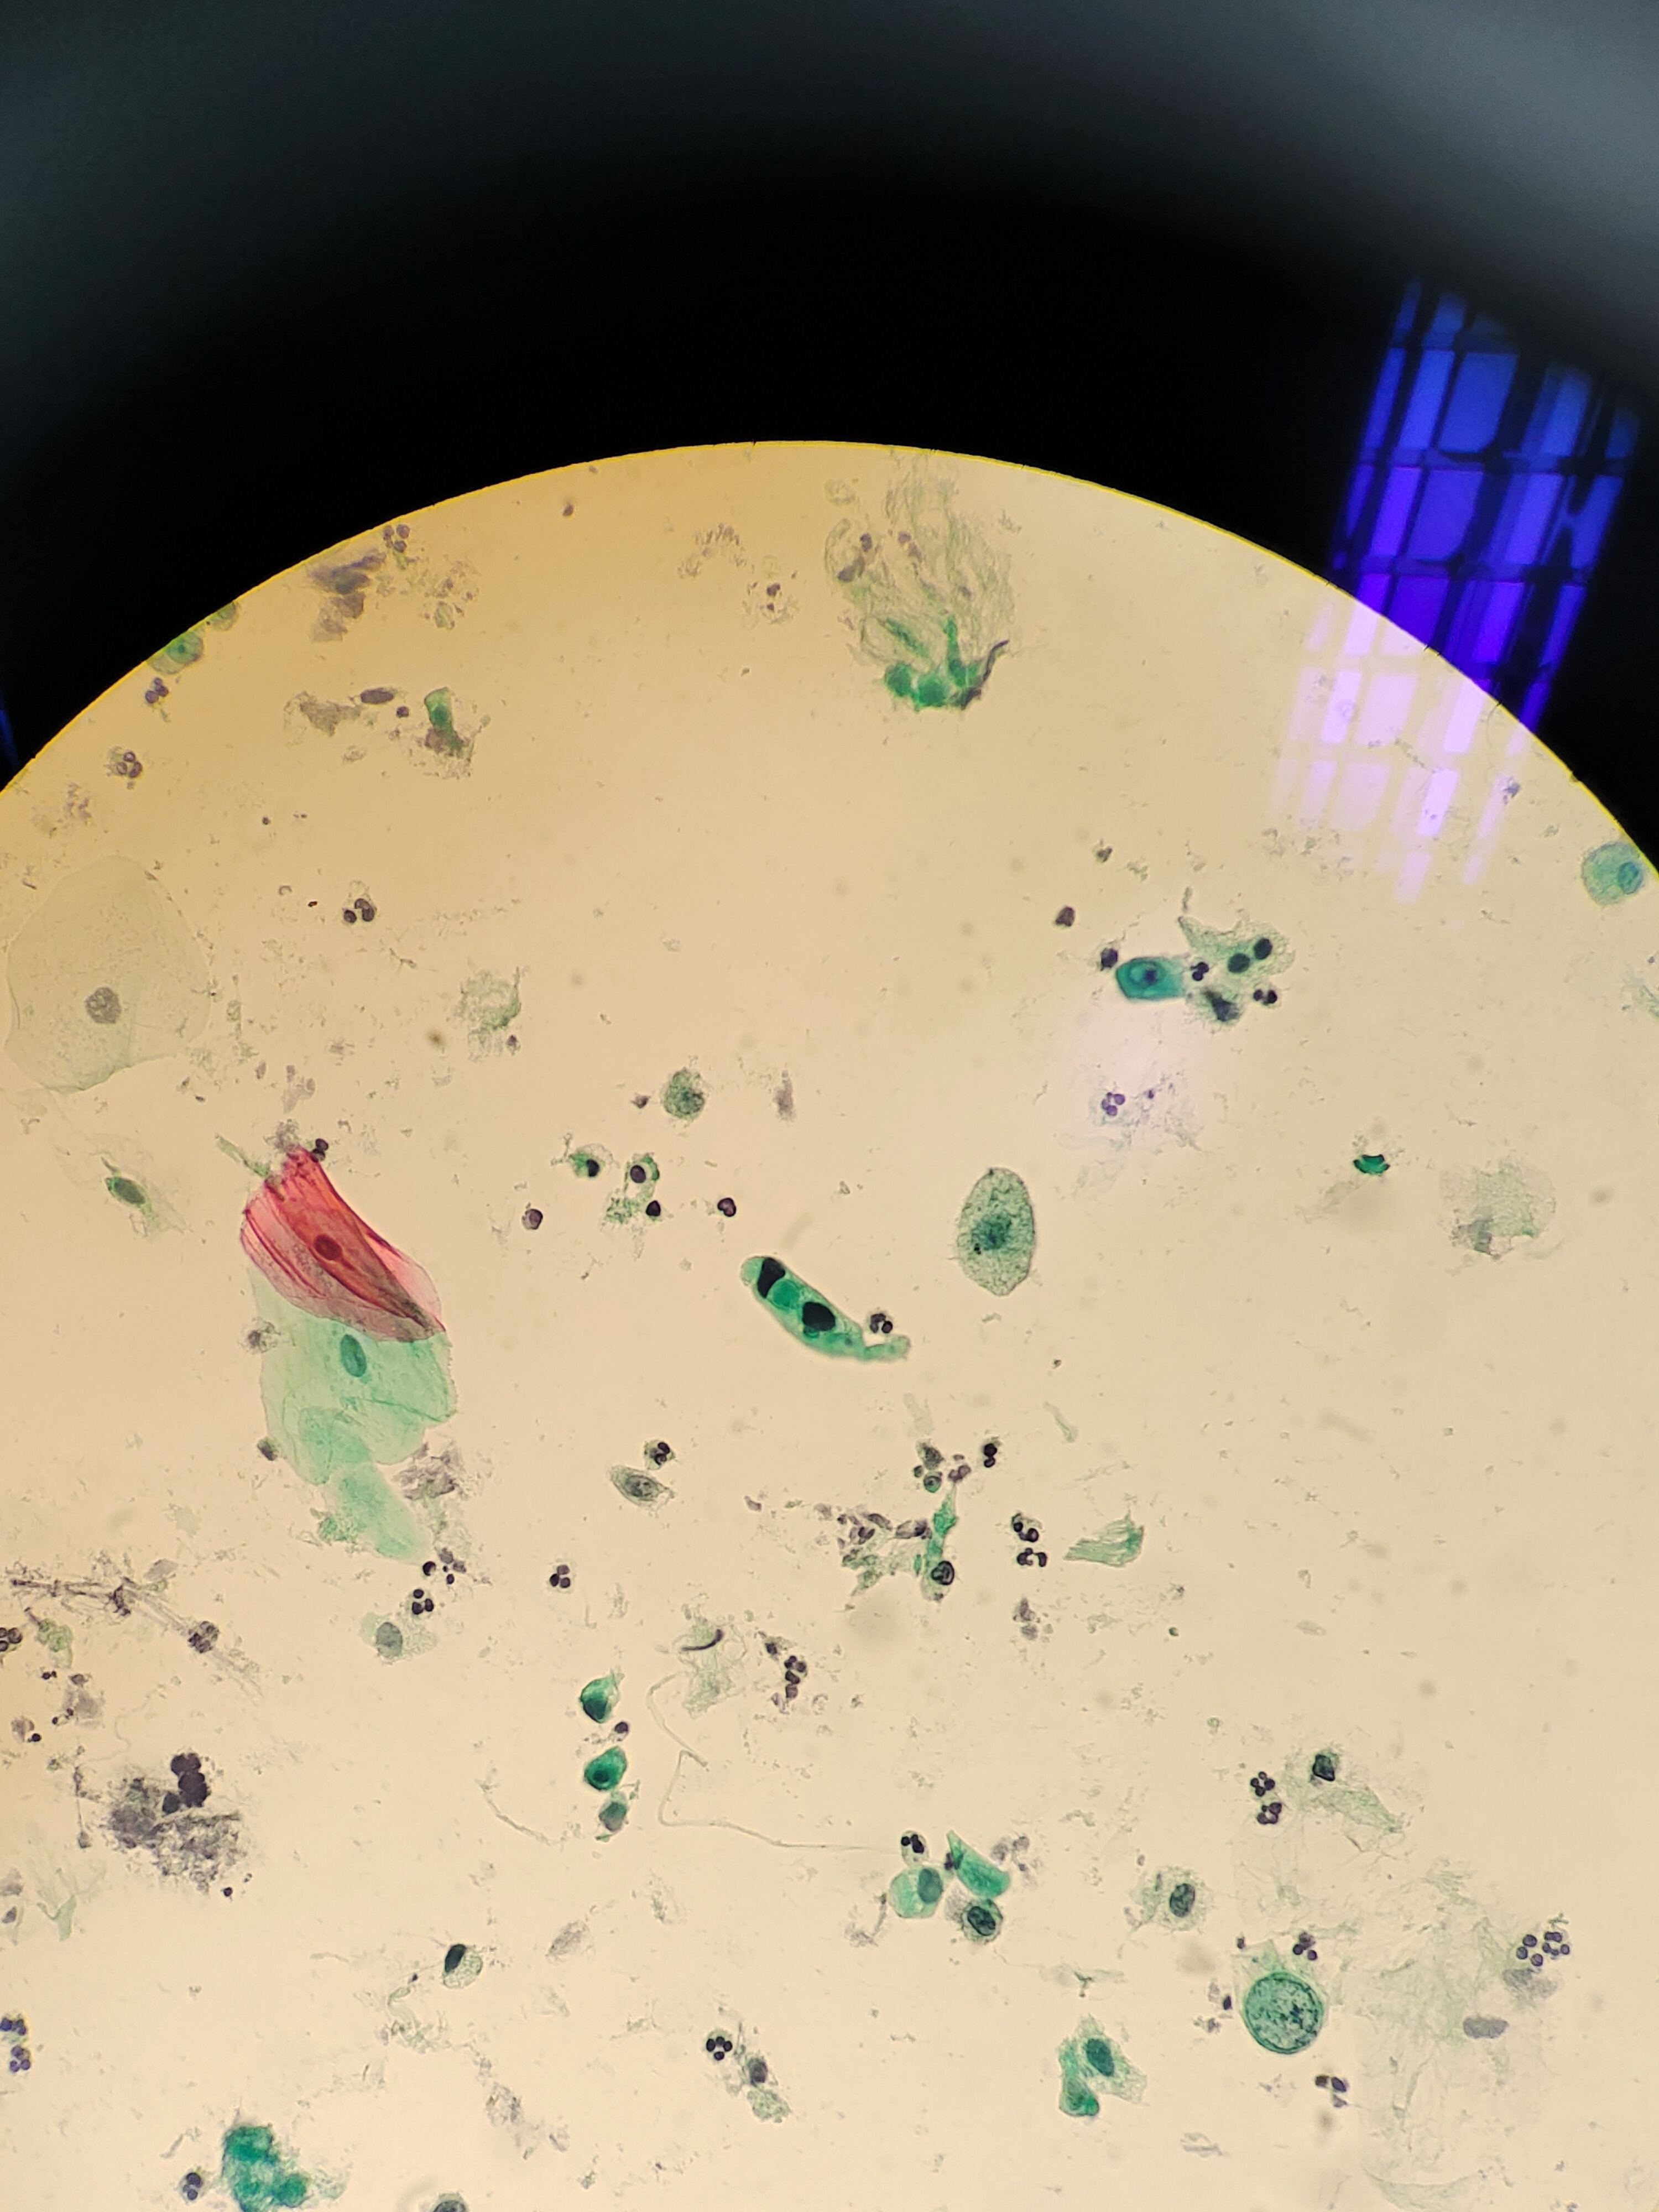

咳嗽咳痰半年余,CT:右下肺门肿块,右肺下叶支气管闭塞,考虑占位可能。老师们,有些核深染细胞,中度核异质?

标本类型

痰

制片方法

液基

染色方法

图1考虑恶性肿瘤细胞

鳞癌

倾向鳞癌。